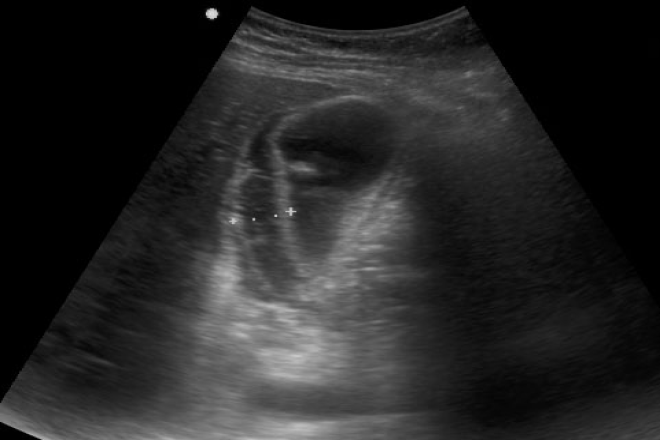

• El estudio más utilizado en la identificación de la vesícula en porcelana fue el Ultrasonido (9 pacientes, 47%) seguido por la Tomografía computada (3 pacientes,16%).

El estudio realizado en nuestro país en el Hospital Central Militar es una gran colaboración para el residente y el medico radiólogo, y considerando a todo aquel medico que utiliza el ultrasonido como herramienta diagnostica, ya que el principal estudio diagnostico utilizado para la identificación de la vesícula en porcelana fue el ultrasonido.

No se tuvieron casos corroborados de vesícula en porcelana y cáncer de vesícula. Por lo tanto, se considera la posibilidad de manejar inicialmente a los pacientes en quienes se identificó la vesícula en porcelana de manera conservadora.

Dada la infrecuencia del padecimiento es importante considerar un seguimiento por imagen del paciente.